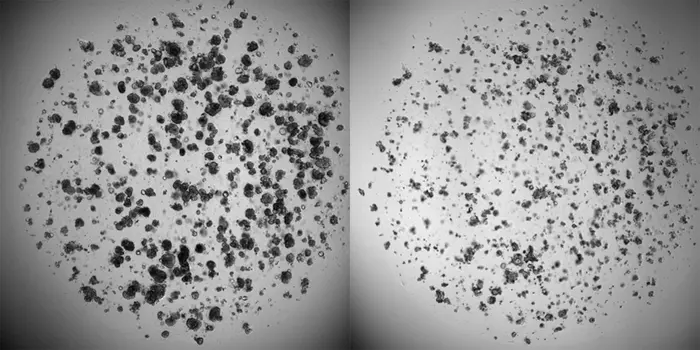

Cancer cells in the laboratory. On the left are cancer cells that have grown for a week without any drugs added. On the right are cancer cells from the same patient after being exposed to chemotherapy.